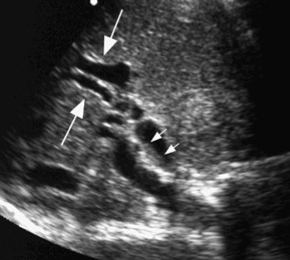

2D US: irregular, circumferential bile duct wall thickening w/ small diverticuli in intrahepatic ducts (beads on string appearance), pinched off intrahepatic ducts from strictures, choledocholithiasis, biliary sludge

color doppler:

DDX: cholangiocarcinoma, choledocholithiasis